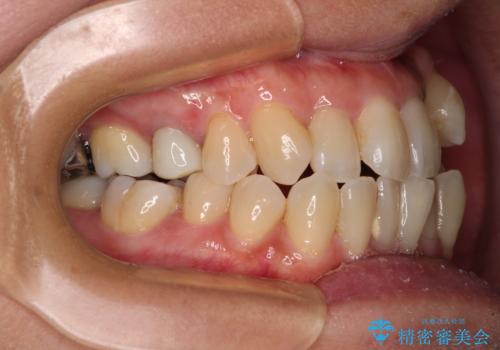

- 前歯のデコボコや八重歯を治したいとのことで来院された患者様です。

受け口傾向の骨格であり、前歯はクロスバイトまたは切端咬合となっており、下顎を中心に歯列全体の後方移動を行い、IPR(歯と歯の間を削る)によってデコボコが解消するように設計し、インビザラインにより治療を行うこととしました。

受け口傾向のインビザライン矯正は比較的治療を行いやすいため、きれいに仕上げることができました。舌の突出癖が顕著であったため、改善のためのトレーニングをしっかりと行っていただきました。